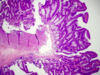

What is this? Histo criteria?

- Sessile serrated adenoma: histo overlap with hyperplastic polyps (differential diagnosis)

- Be on high alert if in the right colon: low threshold for calling these, esp. on the right side

- Malignant potential, but lack typical cytologic features of dysplasia

- Histologic criteria (strict, if on left side) for these lesions include:

1. Serrated architecture throughout full length of the glands, including the crypt base

2. Crypt dilation

3. Lateral growth (boot shape)

What histo is characteristic of Peutz-Jeghers Syndrome polyps?

Sessile serrated adenoma